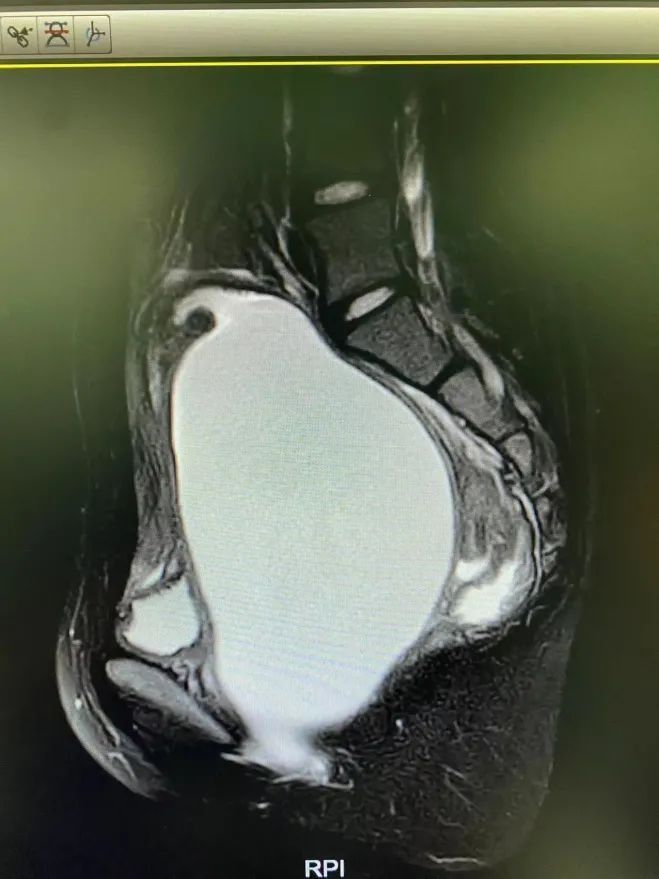

文章插图

术前的盆腔MR:可看到一个巨大包块

言言转诊到浙江大学医学院附属儿童医院急诊科,询问病史得知女孩至今没来过月经,经检查综合考虑为“阴道下段闭锁”,是先天性生殖道畸形的一种,这种疾病在孩子小的时候不容易被发现,在青春期后因经血流出梗阻而出现症状,需要急诊手术解除梗阻、缓解疼痛。